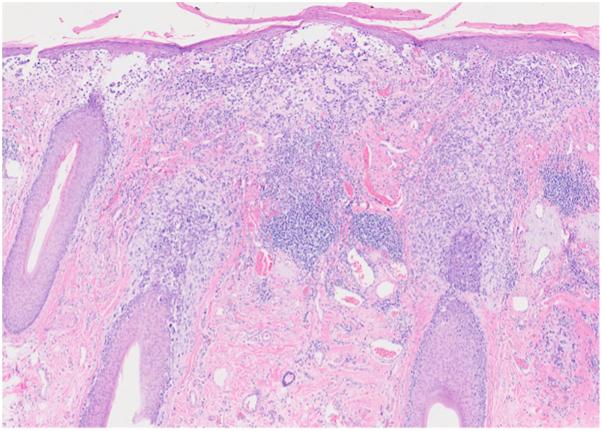

Atypical lentigo maligna melanoma of the chin: A case report.

JAAD Case Rep. 2025 Jun 5;61:7-8. doi: 10.1016/j.jdcr.2025.04.025. eCollection 2025 Jul.

Atypical lentigo maligna melanoma of the chin: A case report.下巴非典型雀斑样痣恶性黑色素瘤:一例报告。